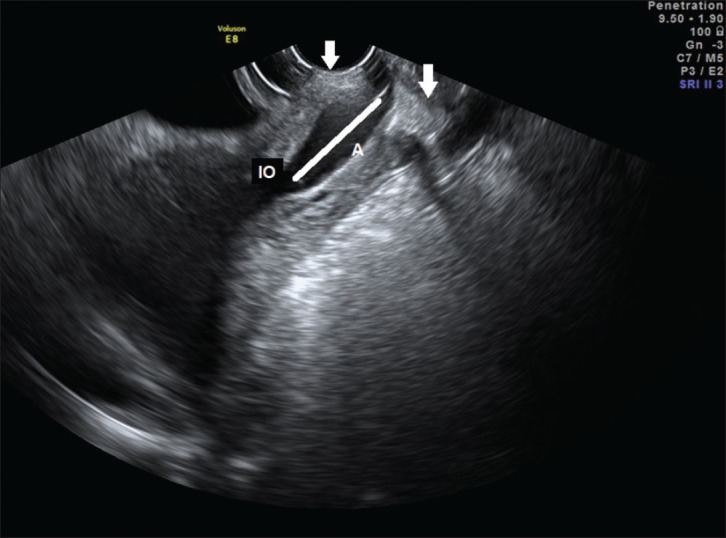

Pre-term labour screening helps identify women who are at risk of delivering before 37 weeks of pregnancy — sometimes before symptoms even start.